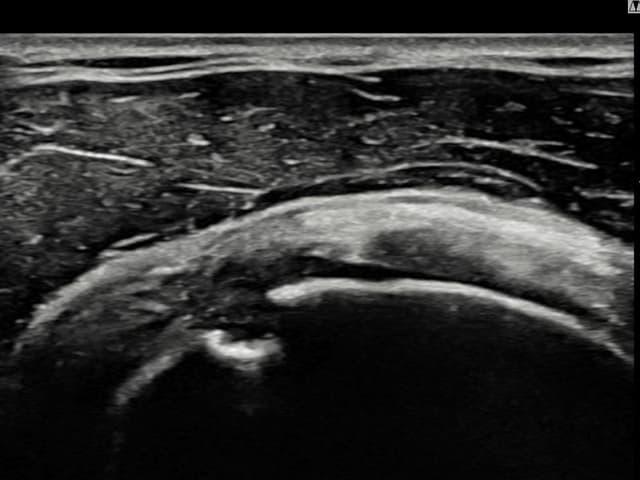

[촬영시기:23.09.01~23.11.03]

[어깨인대 축소봉합술] 우측 어깨 통증이 수개월간 지속되어 내원하셨습니다.